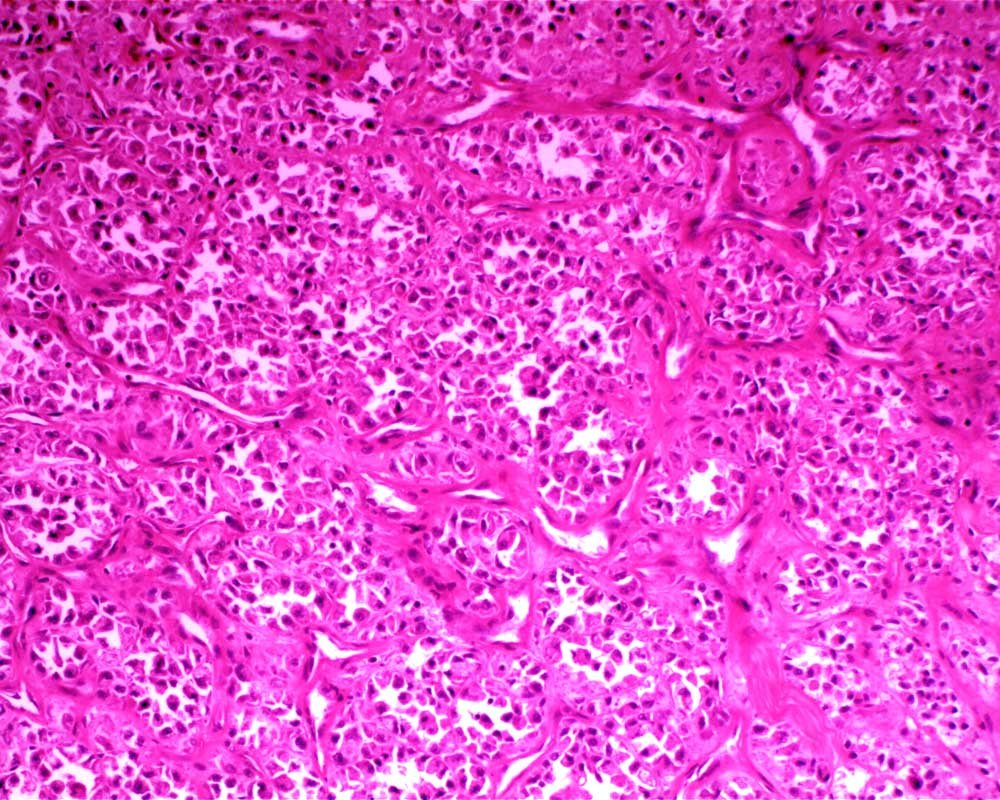

Case: ThighMass

Final Diagnosis: